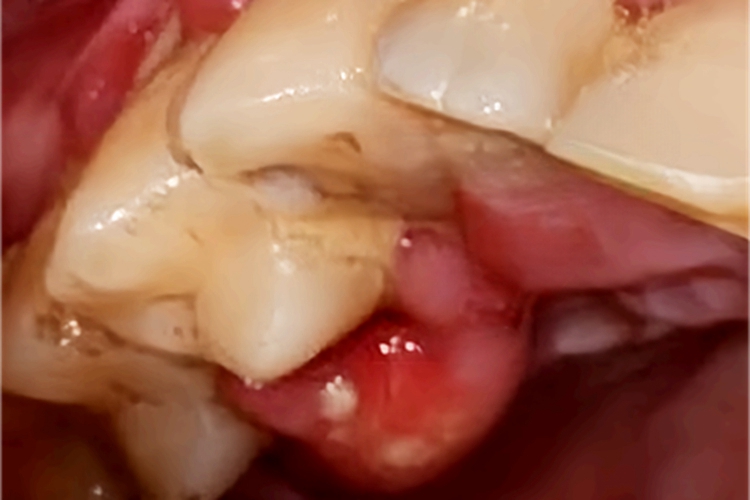

急性牙周脓肿可见牙龈处出现约黄豆大小的脓包,导致患者上嘴唇无法合拢,并且脓包顶端有白色的脓点,波动感明显,患者自觉疼痛。

急性牙周脓肿的治疗原则是止痛、防止感染扩散以及使脓液引流。在脓肿初期脓液尚未形成前,可轻轻清除大块牙石,冲洗牙周袋,将防腐抗菌药引入袋内,必要时全身给以抗生素或支持疗法。当脓液形成且局限、出现波动时,可根据脓肿的部位及表面黏膜的厚薄,选择从牙周袋内或牙龈表面引流。治疗操作应由医生等专业人士进行。